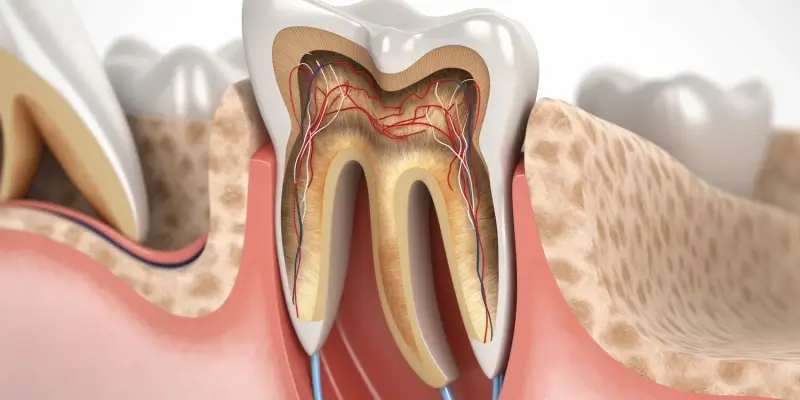

Stomatolog w Legnicy oferuje szeroki zakres usług, które są dostosowane do potrzeb pacjentów. Wśród najpopularniejszych zabiegów znajduje się profilaktyka, która obejmuje regularne przeglądy stomatologiczne oraz czyszczenie zębów. Dzięki tym zabiegom można skutecznie zapobiegać powstawaniu próchnicy i innych chorób jamy ustnej. Kolejnym ważnym obszarem działalności stomatologa jest leczenie zachowawcze, które polega na wypełnianiu ubytków, a także leczeniu kanałowym zębów. W przypadku bardziej skomplikowanych problemów, takich jak usunięcie zęba mądrości, stomatolog w Legnicy również dysponuje odpowiednimi umiejętnościami i narzędziami. Warto również wspomnieć o ortodoncji, która zajmuje się prostowaniem zębów i poprawą zgryzu. Stomatolodzy często współpracują z ortodontami, aby zapewnić pacjentom kompleksową opiekę. Dodatkowo, wiele gabinetów oferuje usługi estetyczne, takie jak wybielanie zębów czy zakładanie licówek, co pozwala na poprawę wyglądu uśmiechu. W Legnicy można znaleźć specjalistów zajmujących się implantologią, którzy pomagają w odbudowie brakujących zębów za pomocą nowoczesnych implantów.

Wśród najczęstszych problemów stomatologicznych zgłaszanych przez pacjentów w Legnicy znajdują się choroby próchnicowe oraz choroby dziąseł. Próchnica to jeden z najpopularniejszych problemów zdrowotnych związanych z jamą ustną i dotyka zarówno dzieci, jak i dorosłych. Nieleczona próchnica może prowadzić do poważniejszych schorzeń, takich jak zapalenie miazgi czy ropnie okołozębowe. Kolejnym powszechnym problemem są choroby dziąseł, takie jak zapalenie dziąseł czy paradontoza, które mogą prowadzić do utraty zębów jeśli nie zostaną odpowiednio leczone. Pacjenci często zgłaszają się także z problemami związanymi ze zgryzem oraz wadami ortodontycznymi; wiele osób decyduje się na noszenie aparatów ortodontycznych w celu poprawy estetyki uśmiechu oraz funkcji żucia. Inne problemy to nadwrażliwość zębów czy przebarwienia spowodowane dietą lub paleniem tytoniu. Warto również wspomnieć o urazach mechanicznych, które mogą prowadzić do złamań lub wybicia zębów; takie sytuacje wymagają natychmiastowej interwencji stomatologicznej.